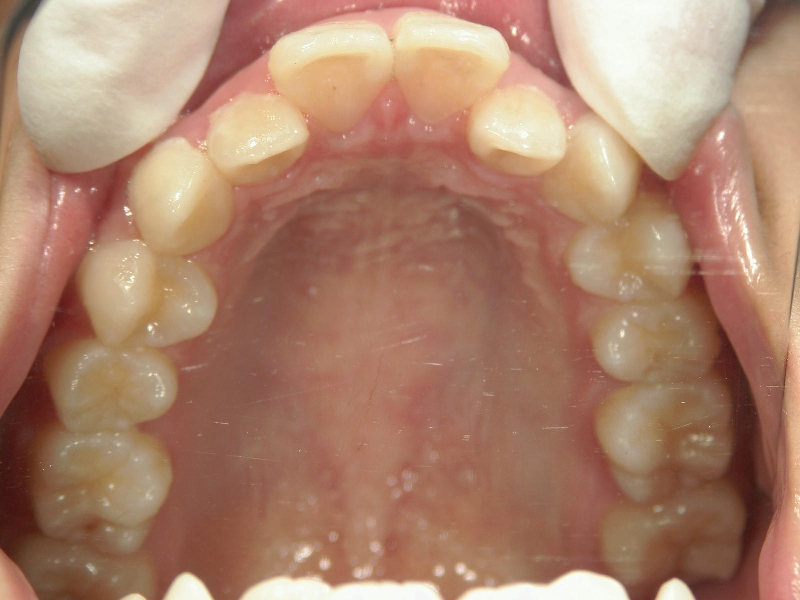

18歳女性 浜松市中区在住

治療期間3年11ヶ月

主訴:上の歯が前に出ている。

矯正歯科 治療前 左右上下4番  計4本抜歯

矯正_灰色.pngno.18_2196_治療前_上.jpg矯正_灰色.png